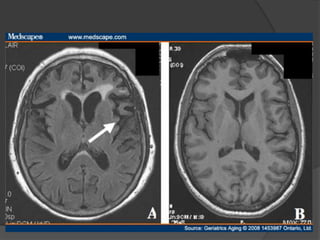

Ventriculomegaly in discordant monozygotic twins seen on T2-weighted MRI scans.

Woolley J , and McGuire P APT 2005;11:195-202

©2005 by The Royal College of Psychiatrists



Enlargement of lateral & third ventricles may be static or

progressive.

Frontal lobe abnormalities, particularly prefrontal gray matter

and orbitofrontal regions.

Parietal lobe abnormalities, particularly of the inferior parietal

lobule which includes both supramarginal and angular gyri.

Subcortical abnormalities i.e. cavum septi pellucidum, basal

ganglia, corpus callosum, and thalamus.

All these structural abnormalities may be static or progressive.